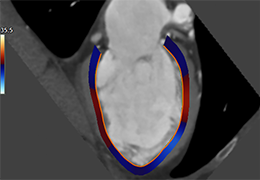

View X-Ray CT & MRI Scans Fast and Easily

Designed for surgeons, Pro Surgical 3D makes it easy to view patient scans quickly. Pro Surgical 3D facilitates the optimal 3D treatment and assessment workflows based on X-ray CT and MRI scans – and best of all, it’s FREE!

Performs 3D reconstruction and volume rendering.

Multi-planar slicing.

Oblique slicing.